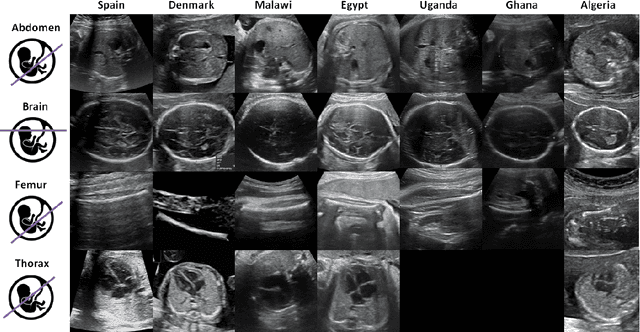

Abstract:Most artificial intelligence (AI) research have concentrated in high-income countries, where imaging data, IT infrastructures and clinical expertise are plentiful. However, slower progress has been made in limited-resource environments where medical imaging is needed. For example, in Sub-Saharan Africa the rate of perinatal mortality is very high due to limited access to antenatal screening. In these countries, AI models could be implemented to help clinicians acquire fetal ultrasound planes for diagnosis of fetal abnormalities. So far, deep learning models have been proposed to identify standard fetal planes, but there is no evidence of their ability to generalise in centres with limited access to high-end ultrasound equipment and data. This work investigates different strategies to reduce the domain-shift effect for a fetal plane classification model trained on a high-resource clinical centre and transferred to a new low-resource centre. To that end, a classifier trained with 1,792 patients from Spain is first evaluated on a new centre in Denmark in optimal conditions with 1,008 patients and is later optimised to reach the same performance in five African centres (Egypt, Algeria, Uganda, Ghana and Malawi) with 25 patients each. The results show that a transfer learning approach can be a solution to integrate small-size African samples with existing large-scale databases in developed countries. In particular, the model can be re-aligned and optimised to boost the performance on African populations by increasing the recall to $0.92 \pm 0.04$ and at the same time maintaining a high precision across centres. This framework shows promise for building new AI models generalisable across clinical centres with limited data acquired in challenging and heterogeneous conditions and calls for further research to develop new solutions for usability of AI in countries with less resources.